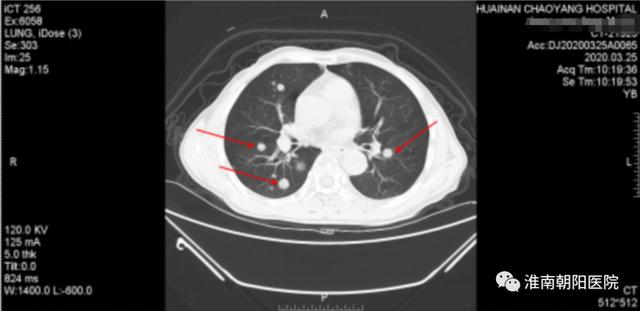

随后患者张大爷又接受两轮化疗,身体状况逐渐变好!但好景不长,肿瘤这个狡猾的家伙居然耐药了,在 12 月份的胃镜检查中我们意外地发现食管内仍然有残存病灶,经过全体专家的会诊后更换了化疗方案治疗,但今年 1 月份复查的时候,医生发现两肺多发转移,病情有进展了!

(图中红色箭头所指的就是肺内的转移灶)

经过淮南朝阳医院肿瘤中心医护人员耐心而温情的安慰后,张大爷决定继续坚持与病魔抗争,之后的 2 个月他又勇敢地接受了 2 周期化疗。但晚期复发性食管癌传统治疗并没有给我们带来惊喜的疗效,张大爷再次出现了明显的进食哽阻感、食欲下降、呕吐等不适症状,身体越来越消瘦, 在今年 3 月份复查的时候两肺多发转移较前进展了,并出现了新的转移灶(右侧胸廓入口处)。

(图为新的转移灶)